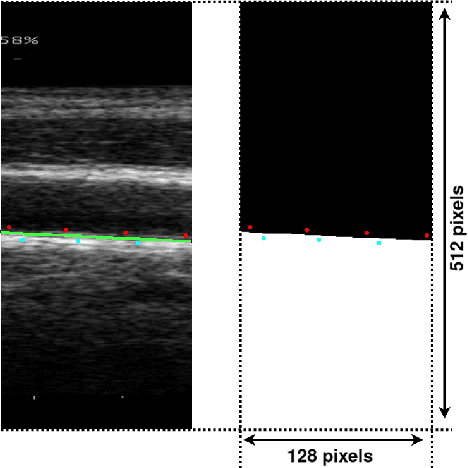

Abstract:The objective of this study is the segmentation of the intima-media complex of the common carotid artery, on longitudinal ultrasound images, to measure its thickness. We propose a fully automatic region-based segmentation method, involving a supervised region-based deep-learning approach based on a dilated U-net network. It was trained and evaluated using a 5-fold cross-validation on a multicenter database composed of 2176 images annotated by two experts. The resulting mean absolute difference (<120 um) compared to reference annotations was less than the inter-observer variability (180 um). With a 98.7% success rate, i.e., only 1.3% cases requiring manual correction, the proposed method has been shown to be robust and thus may be recommended for use in clinical practice.

Abstract:Purpose: The motion of the common carotid artery tissue layers along the vessel axis during the cardiac cycle, observed in ultrasound imaging, is associated with the presence of established cardiovascular risk factors. However, the vast majority of the methods are based on the tracking of a single point, thus failing to capture the overall motion of the entire arterial wall. The aim of this work is to introduce a motion tracking framework able to simultaneously extract the trajectory of a large collection of points spanning the entire exploitable width of the image. Method: The longitudinal motion, which is the main focus of the present work, is determined in two steps. First, a series of independent block matching operations are carried out for all the tracked points. Then, an original dynamic-programming approach is exploited to regularize the collection of similarity maps and estimate the globally optimal motion over the entire vessel wall. Sixty-two atherosclerotic participants at high cardiovascular risk were involved in this study. Results: A dense displacement field, describing the longitudinal motion of the carotid far wall over time, was extracted. For each cine-loop, the method was evaluated against manual reference tracings performed on three local points, with an average absolute error of 150+/-163 um. A strong correlation was found between motion inhomogeneity and the presence of coronary artery disease (beta-coefficient=0.586, p=0.003). Conclusions: To the best of our knowledge, this is the first time that a method is specifically proposed to assess the dense motion field of the carotid far wall. This approach has potential to evaluate the (in)homogeneity of the wall dynamics. The proposed method has promising performances to improve the analysis of arterial longitudinal motion and the understanding of the underlying patho-physiological parameters.